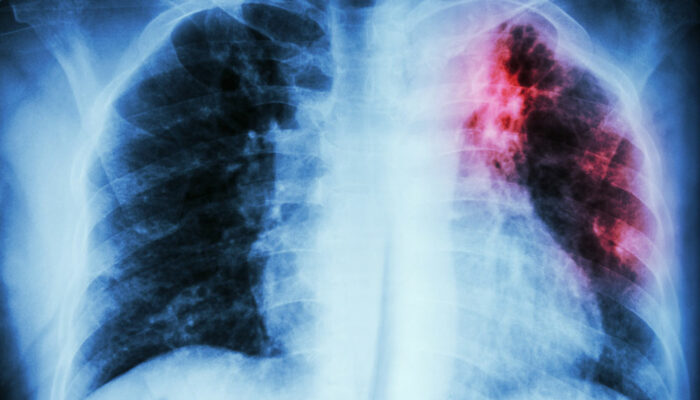

It is an ultrasound test for the heart. - Chest X-ray

This non-invasive technique provides a clear and detailed picture of your heart and lungs which the doctor can examine to detect any problem. - Computerized Tomographic Angiography